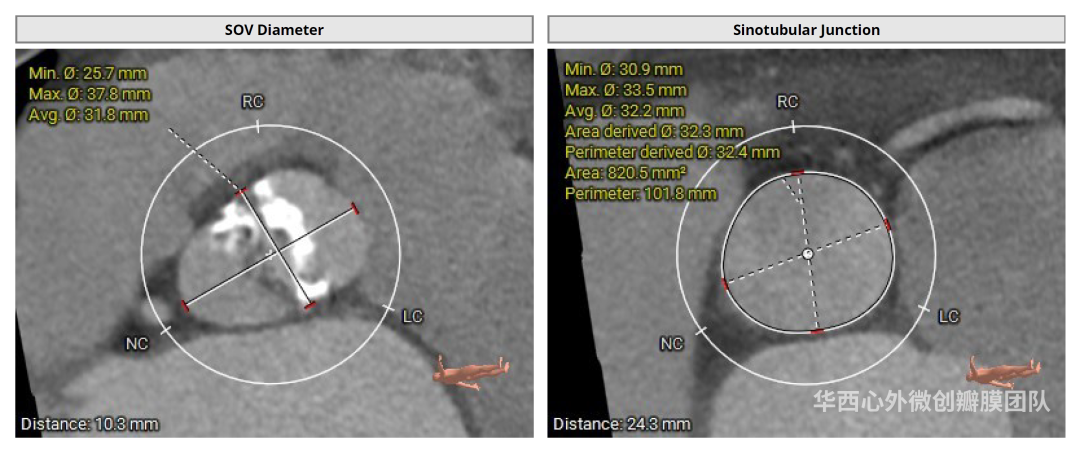

患者镜面右位心,主动脉瓣二叶式,Type 0-lat型,瓣环面积410.3mm²,面积折算直径22.9mm,左冠开口高度14.1mm,右冠开口高度14.7mm,瓣叶增厚,重度钙化,主要分布于瓣叶游离缘,瓣环、流出道、STJ未见明显钙化累及,升主动脉可见扩张,近横位心58°。患者外周血管条件尚可,胸主动脉迂曲、成角90°,未见明显钙化。